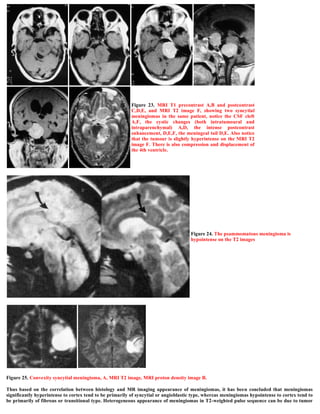

Figure 25. Convexity syncytial meningioma, A, MRI T2 image, MRI proton density image B.

Thus based on the correlation between histology and MR imaging appearance of meningiomas, it has been concluded that meningiomas

significantly hyperintense to cortex tend to be primarily of syncytial or angioblastic type, whereas meningiomas hypointense to cortex tend to

be primarily of fibrous or transitional type. Heterogeneous appearance of meningiomas in T2-weighted pulse sequence can be due to tumor

vascularity, calcifications, and cystic foci.

Elster et al 5 reported a strong correlation between tumor histology and tumor intensity on T2-weighted images compared with those of the

cortex. Meningiomas are classified into four basic subtypes: fibroblastic, transitional, syncytial, and angioblastic. 4,6 Elster et al 5 have stated

that meningiomas significantly hyperintense to cortex tend to be primarily of syncytial or angioblastic type, whereas meningiomas

hypointense to cortex tend to be primarily of fibrous or transitional type.